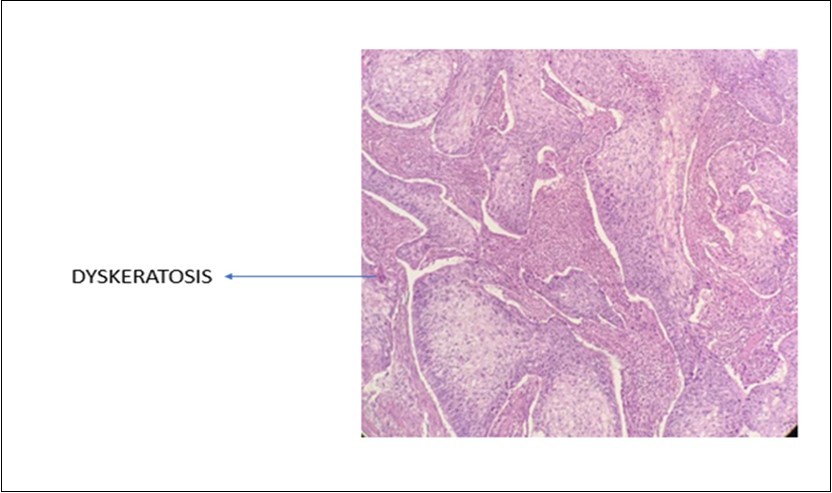

A 42-year-old gentleman, ex-smoker with underlying diabetes mellitus came to our clinic for right neck swelling for about 10 months. The swelling was gradually increasing in size and was giving occasional pain to the patient. But, there were no obstructive symptoms nor a history of prior exposure to radiation. Upon examination, there was a 2x2cm firm, fixed and non-tender swelling palpable at level II of right neck, with no skin changes seen. The facial nerve was intact and the oral cavity was clear. Proceed with flexible scope, there was no mass seen, and laryngeal structures were normal. Fine needle aspiration revealed normal salivary gland elements. A contrasted-CT scan reported a deep lobe parotid gland mass with non-opacification of the right internal jugular vein which could be from compression or thrombosis. [Figure 3] A wedge biopsy was performed subsequently which reported as squamous cell carcinoma, moderately-differentiated. [Figure 4, Figure 5 & Figure 6] Given the malignancy reported, a right total parotidectomy with right selective neck dissection was performed. Post-operatively, the patient developed House-Brackmann grade II facial nerve palsy. Histopathology showed evidence of squamous cell carcinoma with no involvement of adjacent nodes. A final diagnosis of T3N0M0 squamous cell carcinoma of the parotid gland was established. The patient was then referred to the oncology team for chemoradiation. Currently, the patient has completed adjuvant radiotherapy with no signs of recurrence observed so far at six months follow-up.

Figure 4.Photomicrograph show presence of dyskeratotic cells in SCC of parotid (x40 high power field)

Meanwhile, for primary SCC lesions, the malignant cells show many cytoplasmic processes and desmosomes. Also, the cells have intermediate filaments in their cytoplasm with no secretory granules. These features usually help differentiate primary SCC from the similar-looking MEC. Moreover, SCC malignancies have distinct tumor markers that help pathologists in differentiating it from the rest of the tumors. These tumor markers are p40, CK 5/6 and p63. The use of these markers is as evident in this article.